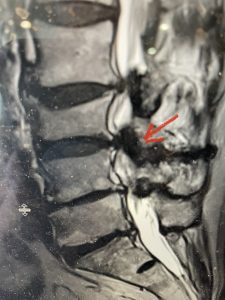

The next patient is a 71 year-old male with a two-year history of low back pain and lower extremity pain, numbness and weakness. His left leg was worse than the right. He had had five epidurals with no improvement. He also had tried physical therapy and medicines but nothing helped. He also felt that over the last three weeks he had gotten worse. He also had recently had some decreased sensation of bladder fullness and difficulty with bowel movements. MRI revealed a very tight L2-5 stenosis with an extruded L3-4 disc fragment (Fig 3).

(Figs 3a) Sagittal (a) and Axial (b) T2-weighted lumbar MRI demonstrating severe spinal stenosis L2-5 (arrow)and extruded disc at L3-4 on axial image (arrow)

(Fig 3b)

He had concentric severe stenosis with severe compression of the lateral recess and foramen at L3-4 secondary to the superimposed disc herniation. The fact that he had gotten worse with subtle cauda equina features with an extremely tight canal, he underwent a decompressive laminectomy. We also augmented his laminectomy with an in situ fusion from L3-5 as he was relatively young, with more time to reform arthritis, and had been unstable enough to extrude a disc fragment. By placing “bone dust” or bone material along the sides of the spine, specifically laying it across the transverse processes after they have been drilled to bleeding bone, you provide an environment where bone formation is induced to connect the segments, stabilize them, and thereby reduce the signal to make more arthritis as that signal is still present despite the laminectomy. What was interesting was that we encountered a large extruded disk fragment that was significantly contributing to his compression which is often not found in patients in this age bracket. Post operatively he had much improvement of leg pain.